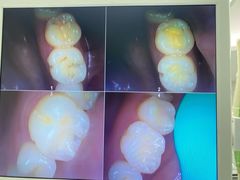

• 牙博士口腔品牌连锁(杨浦店)

• -牙博士口腔品牌连锁(杨浦店)

【已注销用户】 | 25-07-17